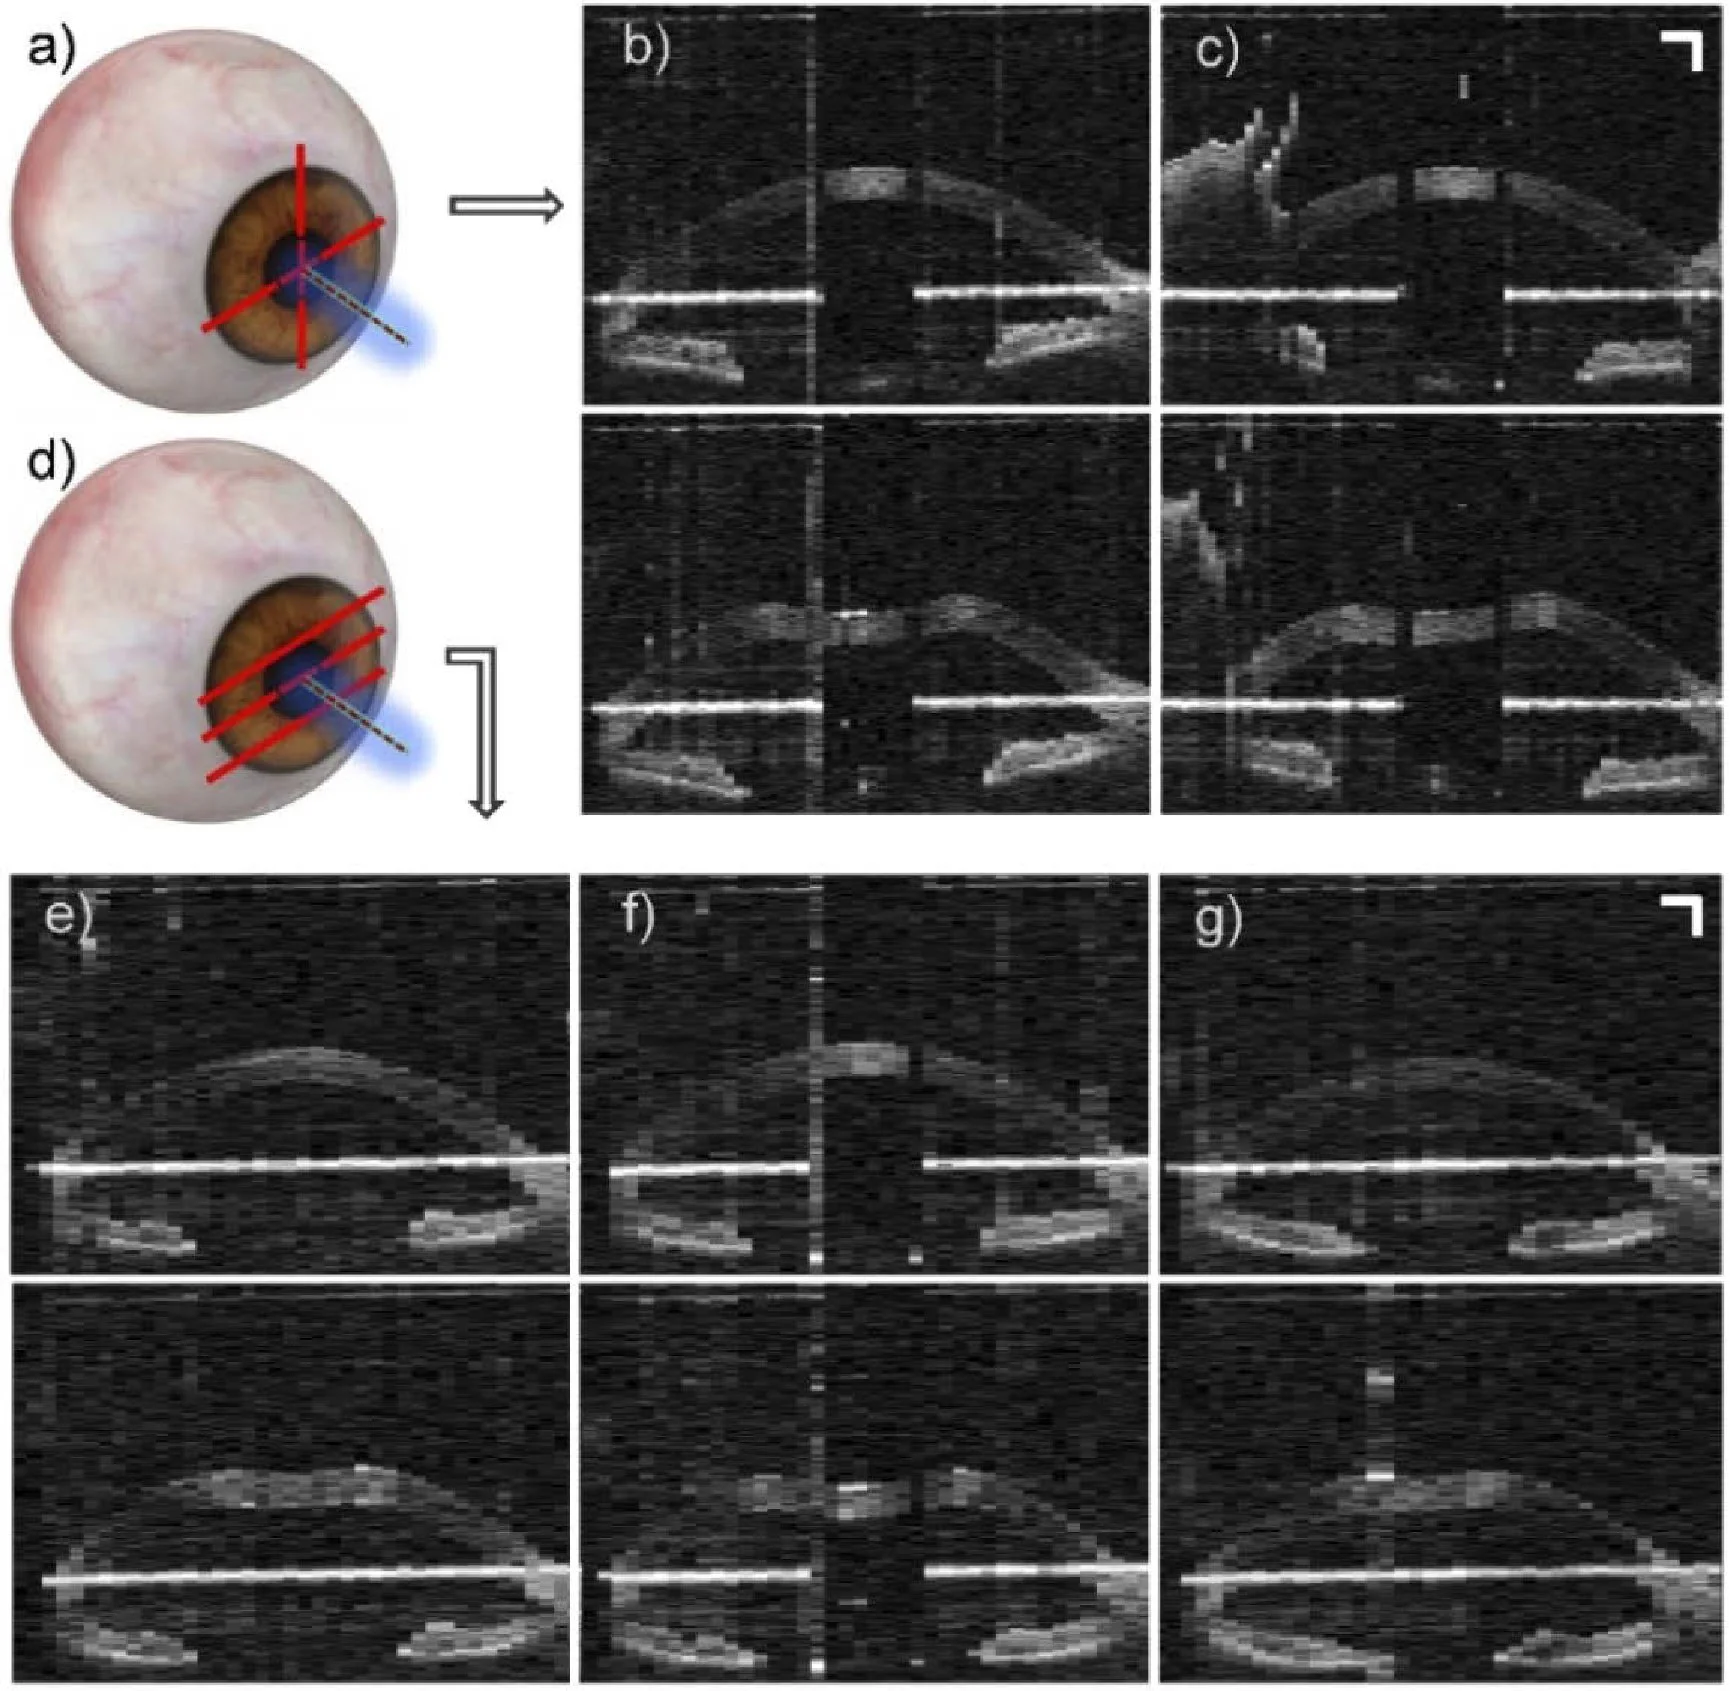

(a) “Cross-meridian” scan pattern schematic. OCT in vivo human corneal deformation frames before air-puff (top) and at maximum deformation (bottom), for (b) horizontal meridian and (c) vertical meridian. (d) “Three horizontal planes” scan pattern schematic. OCT in vivo human corneal deformation frames before air-puff (top) and at maximum deformation (bottom), for (f) the horizontal meridian, (e) 2 mm above, and (g) 2 mm below. Scale bars: 1 mm